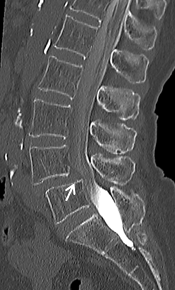

【術前】

CT検査で関節突起部に腰椎分離症を認めています。若年者の腰痛の原因となります。

【術後】

CT検査で関節突起部の骨移植を伴う分離部修復術を施行し骨癒合が得られています。